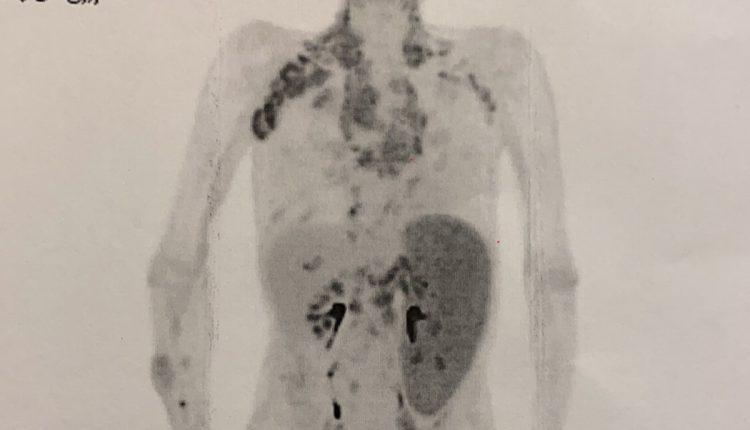

年過70歲的德叔,長年體弱多病,因疲於出入醫院,便養成大病才找醫生,小病就自行處理的習慣。有次發現腋下有腫塊,並不以為意。過些時日脖子也長出硬塊,因沒什麼特別痛感,所以再次忽略。後來肚子開始腫痛,他以為是胃潰瘍發作,仍持續在家休養未即時就醫。直到疼痛難耐才就醫,一檢查竟是淋巴癌第四期,擴散到了脾臟,脾臟腫大到比肺還大,導致肚子腫痛。嚇壞了醫生和所有的家人,於是緊急進行各項治療。

淋巴癌號稱「沉默的癌症」,因為它的初期症狀不明顯,患者往往不知道自己罹患疾病,若未進一步接受診斷與治療,等到症狀嚴重時往往已進入晚期,提升治療難度。淋巴癌的常見症狀有以下六種: